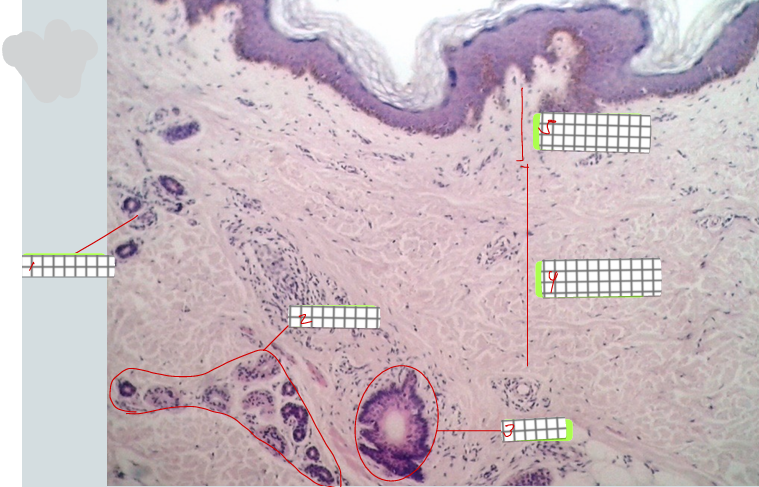

Human palm skin

papillary layer of dermis

dermal papillae

epidermal ridge

reticular layer of dermis

sweat gland

specimen:

label